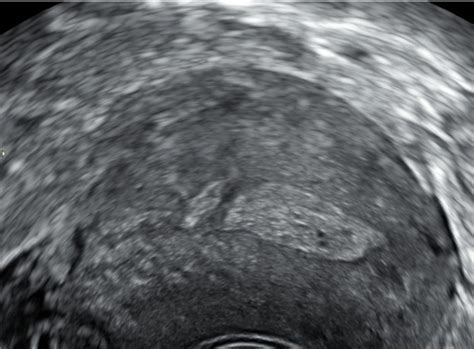

Pregrada v maternici je prirojena anomalija, ki nastane med razvojem ženskega zarodka. V zgodnjih fazah razvoja se maternica oblikuje iz dveh cevi, ki se nato v spodnjem delu združita. V primeru pregrade v maternici ta združitev ni popolna, kar ima za posledico, da v maternični votlini ostane del ali celotna pregrada. Ta pregrada je vedno locirana po sredini maternične votline in poteka od vrha navzdol. Njihova debelina in dolžina se lahko razlikujeta, kar vpliva na stopnjo težav, ki jih povzročajo. Včasih je težko ločiti med pregrado in sedlasto maternico, pri čemer je za dokončno diagnozo običajno potrebna histeroskopija. Majhna pregrada, na primer do 1 cm, je sicer majhna, vendar je ključno dejstvo njeno obstajanje, ne le njena velikost.

Odločitev o odstranitvi pregrade v maternici je kompleksna in pogosto predmet različnih mnenj med ginekologi. Glavna dilema se pojavi, ko je pregrada odkrita pred prvo zanositvijo.